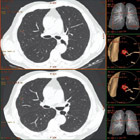

CT screening (rano otkrivanje) karcinoma pluća

Karcinom pluća je najčešći karcinom kod muškaraca, pa se ranom otkrivanju te bolesti pridaje velika važnost. Uvođenje višeslojnog CT-a (MSCT) u kliničku praksu omogućilo je i screening (rano otkrivanje) karcinoma pluća. Pregled je namijenjen onima koji su visokog rizika za karcinom pluća i omogućava otkrivanje izrazito malih čvorova u plućima, koji mogu biti prisutni, a da nisu vidljivi na standardnom rtg snimku pluća. Rano otkrivanje ovih promjena može dramatično poboljšati uspješnost liječenja karcinoma pluća.

Šta mogu očekivati od rezultata testa?

Ako je screening CT uredan dalje ispitivanje nije potrebno.

Ako se nađe čvor u plućima, može biti potrebno uraditi detaljniji-dijagnostički CT pluća, s kontrastom. Često se za čvorove koji su nadjeni pri preventivnom pregledu ispostavi da su granulomi ili ožiljci kada se uradi detaljniji/dijagnostički CT pluca ili se radi o čvorovima benignih karakteristika, koji se potom prate u određjenim periodima da bi se bilo sigurno da se radi o zaista benignoj promjeni.